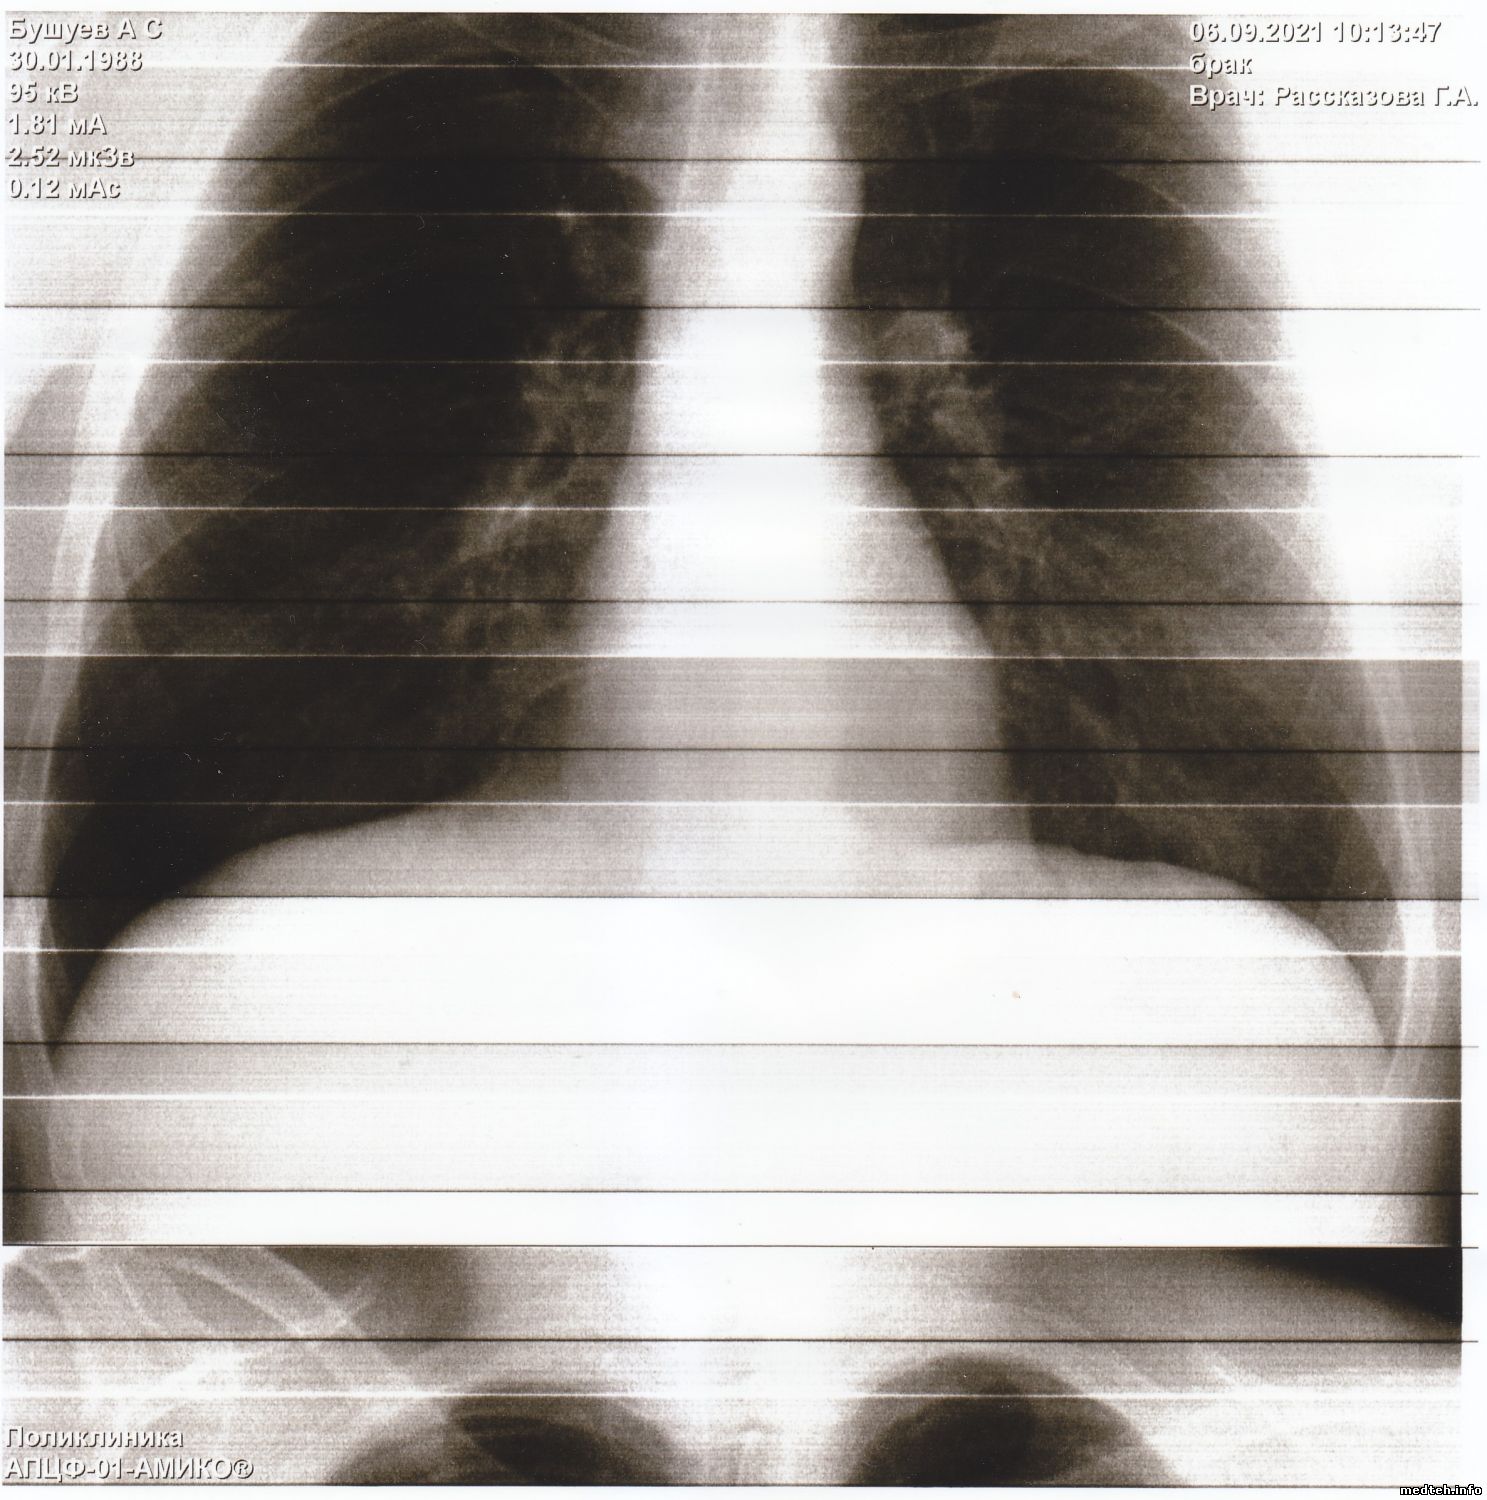

Здравствуйте коллеги.

Прислали снимки из другого города, просят помочь устранить неисправность.

Аппарат я не видел. По снимкам, конечно, не установишь причину, может у кого была такая проблема.

Появились горизонтальные и вертикальные полосы на снимках, делает снимки - смещённые на половину. Снимок есть, видны легкие и все остальное, но полосы очень мешают докторам.

Подскажите что можно сделать в данной ситуации.

Друзья, думаю, вы знаете решение этой проблемы.

Фото прилагается.

Всё решилось просто - тренировка - калибровка и нормальные снимки.